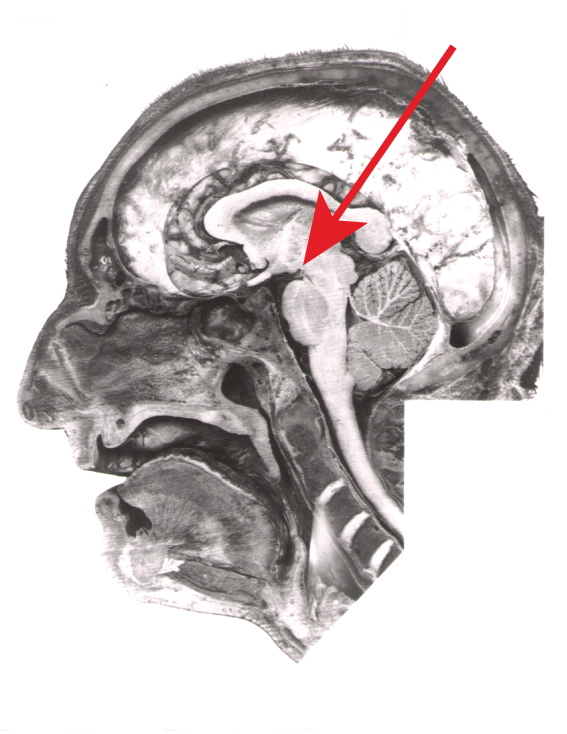

FIGURE 2.8

Case Study Data

The damage in this region to Patient N.A. provided new insights into how the brain creates memories.

One famous case study in psychological science involves a young American man, referred to as N.A., whose unusual injury impaired his memory (Squire, 1987). After a brief stint in college, N.A. joined the Air Force and was stationed in the Azores. One night, he was assembling a model airplane in his room. His roommate was joking around with a miniature fencing foil, pretending to jab at the back of N.A.’s head. When N.A. turned around suddenly, his roommate accidentally stabbed him through the nose and up into his brain (FIGURE 2.8). Although N.A. seemed to recover from his injury in most ways, he developed extreme problems remembering events that occurred after the injury. He could remember events before his accident, but he simply could not remember new information. He had trouble watching television because he would forget the story lines, and he had difficulty having conversations because he would forget what others had just said. The case study of N.A. spurred researchers to generate new hypotheses about how the brain supports memory.